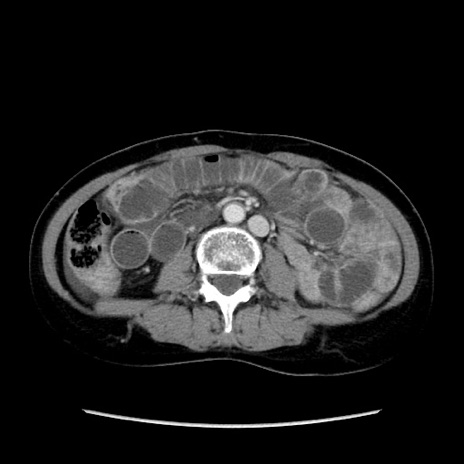

症例32(横断像)

【症例】40歳代 女性

【主訴】上腹部痛、嘔気・嘔吐

【現病歴】約9時間前頃から急に上腹部痛、嘔気、嘔吐が出現。改善しないため救急要請。

【既往歴】子宮頚癌(広汎子宮全摘術、放射線療法)、腸閉塞

【身体所見】腹部:平坦、軟、腸雑音亢進、上腹部を中心に腹部全体に圧痛あり。

【データ】WBC 8400、CRP 0.03